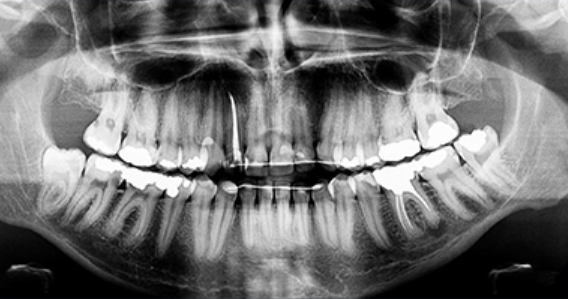

사랑니는 어금니 뒤쪽에서 나오는데

사랑을 느낄 만한 나이인 10~21세쯤 에 난다고 해서 사랑니라고 부르며

다른 명칭으로는 세번째 나는 큰 어금이라고 제 3대구치라고 불립니다.